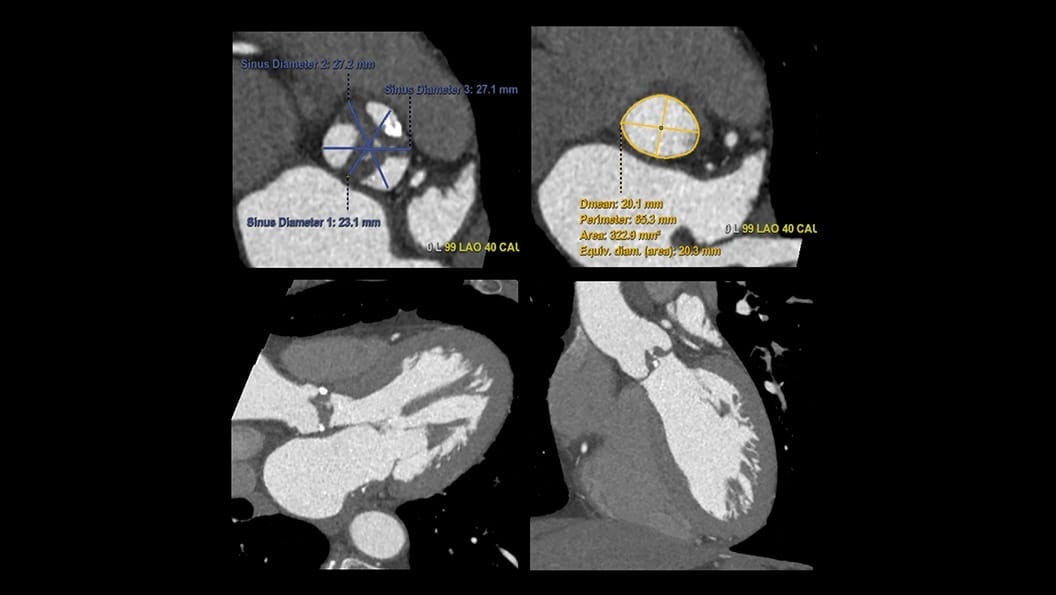

CT-Guided Interventional Care

Since becoming an important step in the patient care pathway and heart care guidelines, CT images are an invaluable tool in the cath lab, guiding procedures for precise personalized care.